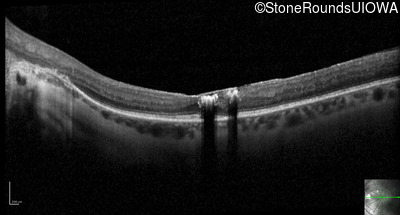

Optical Coherence Tomography - Right - 20/25

Exemplar / OCT Stack

Optical Coherence Tomography - Left - 20/40 +1